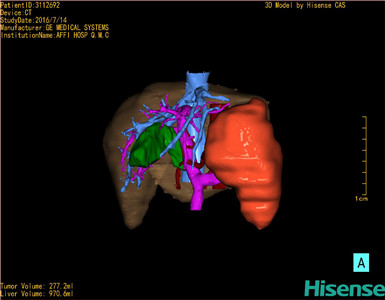

将0.625mm双源薄层CT资料的静脉期和动脉期Dicom格式文件导入海信CAS系统。

通过调节窗宽窗位调整CT序号,对肿瘤,肝实质,胆囊,下腔静脉,肿瘤,肝动脉、门静脉及肝静脉等进行三维重建;系统自动计算肿瘤体积和肝脏体积。

模拟手术操作,自动计算切除肿瘤体积。肝脏体积为970.6ml,肿瘤体积为277.2ml,肿瘤体积为肝脏体积的28.6%,通过比对60-70岁正常肝脏体积为1262.7±284.31 ml,通过术前模拟手术,精准判断切除后剩余肝脏体积能耐受,避免肝衰竭发生。

术前手术方案的规划。

术前三维重建:

重建图片